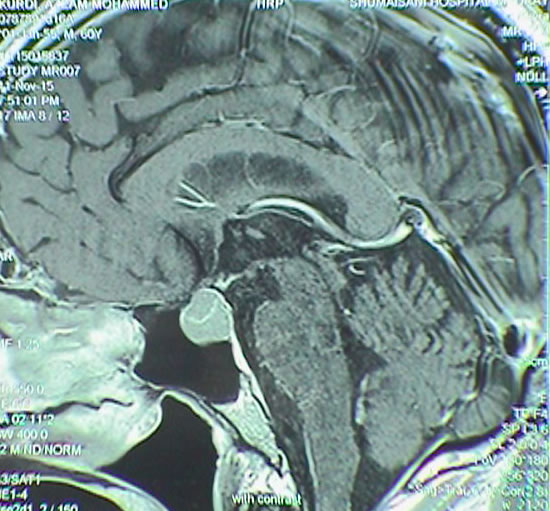

Fig-8: MRI showing the cystic craniopharyngeal cyst pushing the mesencephalon inferior.